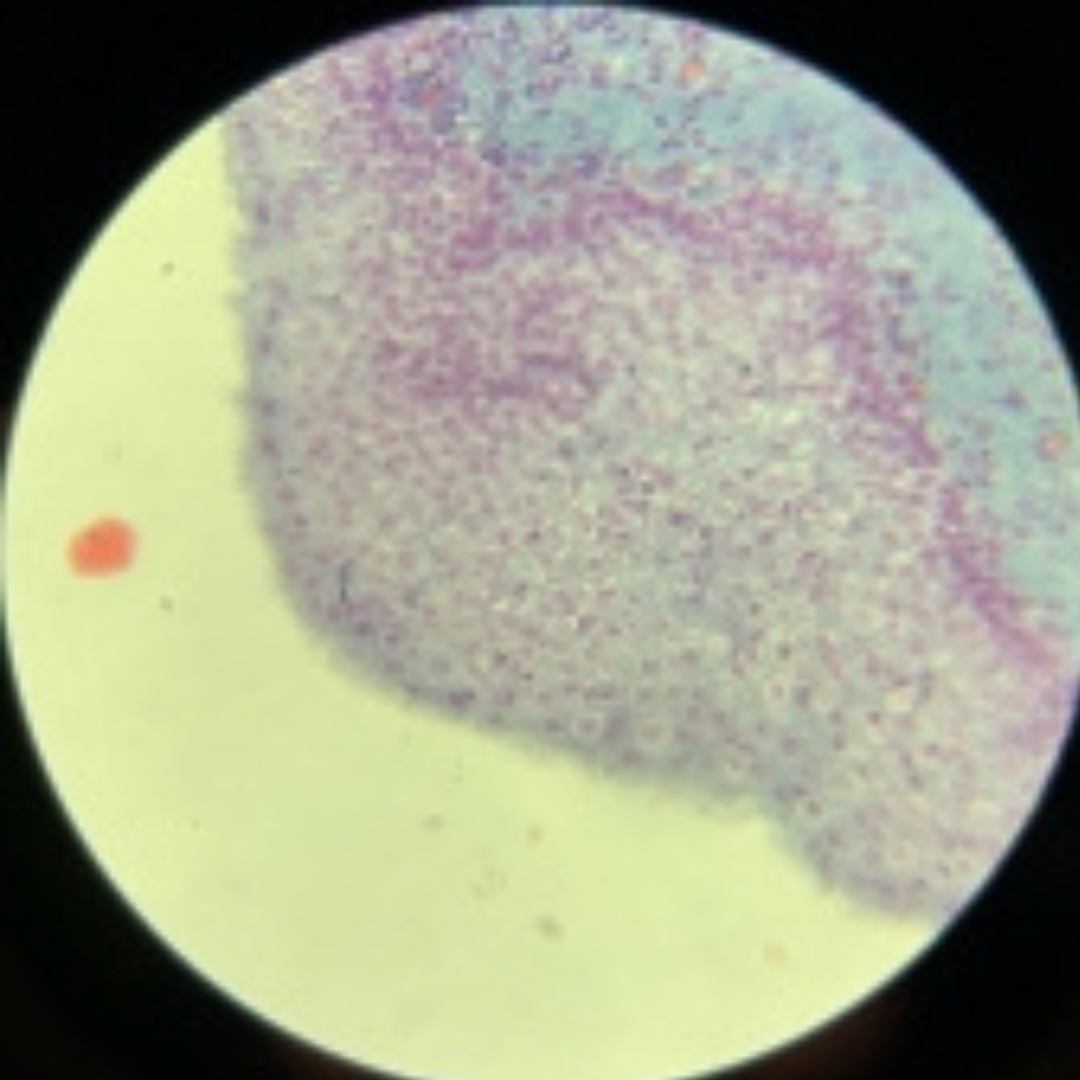

Reticular Connective Tissue (Lymph Node)